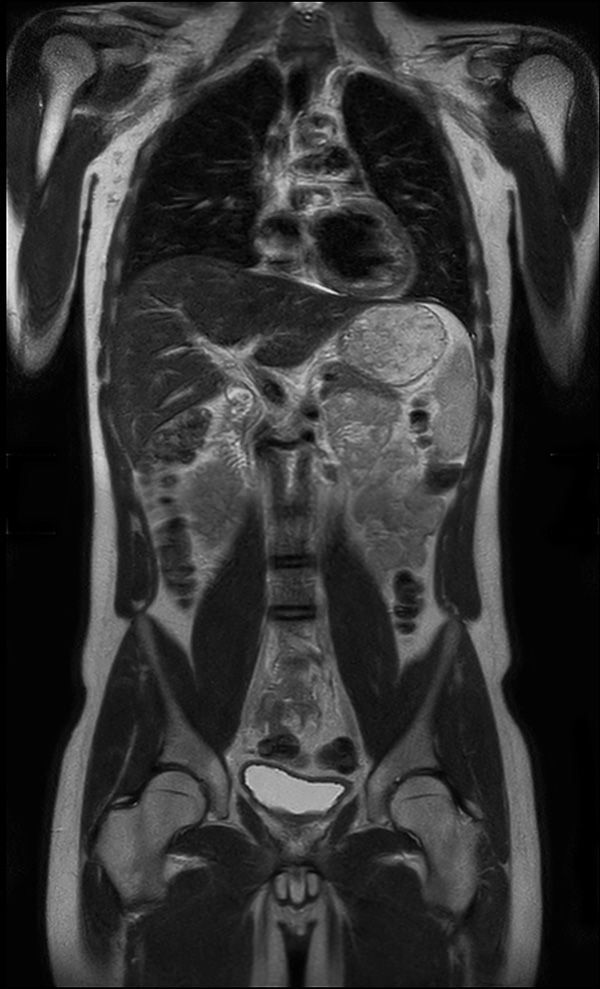

Coronal T2w TSE (MobiView)